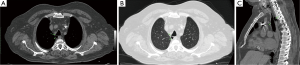

Multidetector computed tomography (MDCT) is the best imaging method to demonstrate tracheal DV. It is useful for evaluating the localization, size, contour, and wall thickness of tracheal DV. Communication between the DV and trachea can also be seen with MDCT. Characteristic MDCT findings of tracheal DV include a thin-walled air sac at the paratracheal area with or without communication to the tracheal lumen (7). MDCT also can be use to distinguish between congenital and acquired lesions, depending on the presence or absence of cartilage and the size of the neck of the DV (5). Slice thicknes of the chest MDCT should be thinner than 1 mm for detailed, accurate evaluation of tracheal DV. Axial, coronal, and sagittal multiplanar images can be obtained with thinner (≤1 mm) slice thicknesses (Figure 1). Connection between DV and the trachea can be evaluated easily with these multiplanar images (Figure 2).

Kurt et al. (4) demonstrated communication between the tracheal lumen and diverticula in 53 (12.9%) of the 412 tracheal diverticulum cases. In addition, Polat et al. (8) demonstrated communication between the tracheal lumen and air cysts in 50 (16.6%) of the 301 PTACs.